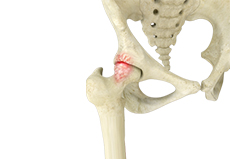

Gluteus Tendon Tear

The gluteal muscles (situated in the buttocks) are necessary for the stability and movement of the hip joints. The tendons of two gluteal muscles (gluteus medius and gluteal minimus) are attached at the outer hip region and are often called the “rotator cuff of the hip.” These tendons may be subject to injury or tearing due to various reasons. Since these gluteal muscles are involved in abduction (movement of your leg away from the midline of the body), the tears are also called abductor tendon tears.

Gluteus Medius Tear

A gluteus medius tear is the partial or complete rupture of the gluteus medius muscle due to severe muscle strain.